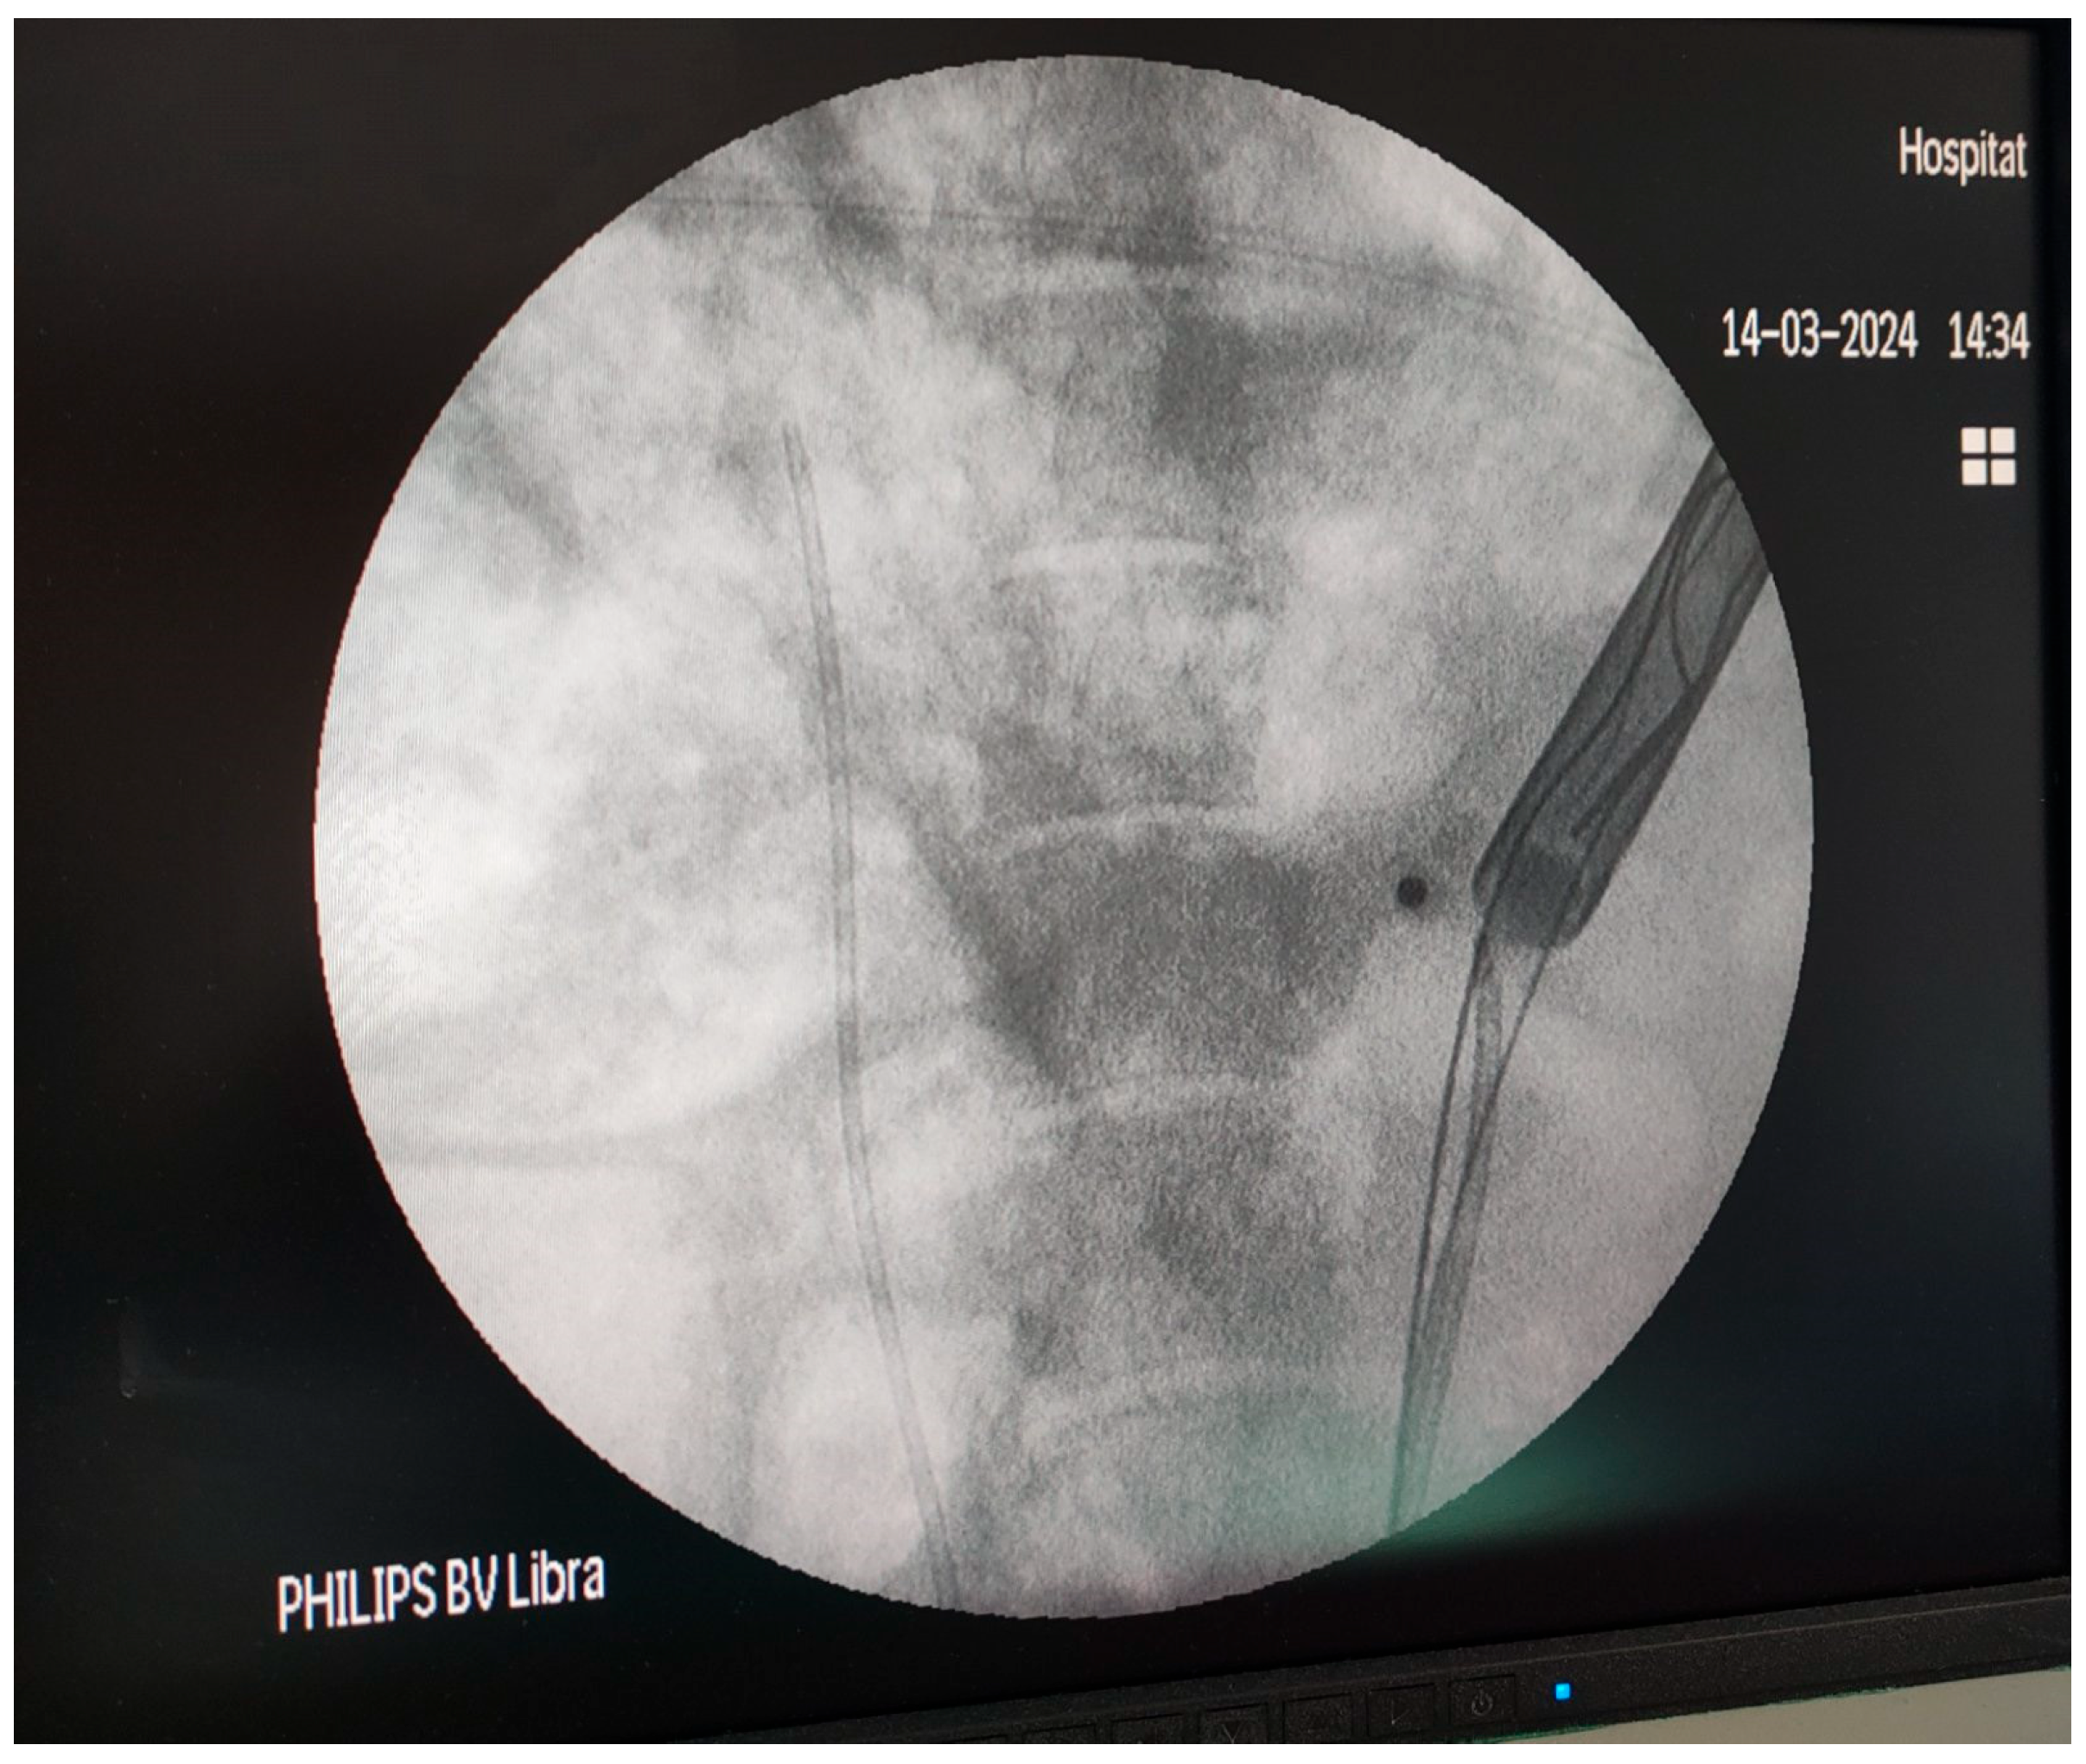

2.3. Operating Room Setup and Technique

2.4. Measurement of the Intrarenal Pressure